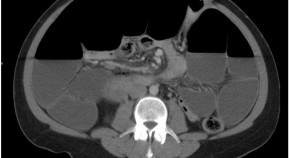

• A 33-year-old woman with a history of paroxysmal nocturnal hemoglobinuria (PNH) presented with abdominal pain, nausea and vomiting, accompanied by duodenal wall thickening seen on an abdominal CT scan and an ischemic-looking duodenal mucosa as visualized by endoscopy. She was diagnosed as having small bowel ischemia complicating PNH. Treatment with warfarin was started, but ischemic episodes recurred. Treatment with eculizumab was, therefore, proposed. This case highlights this rare gastrointestinal complication of PNH.